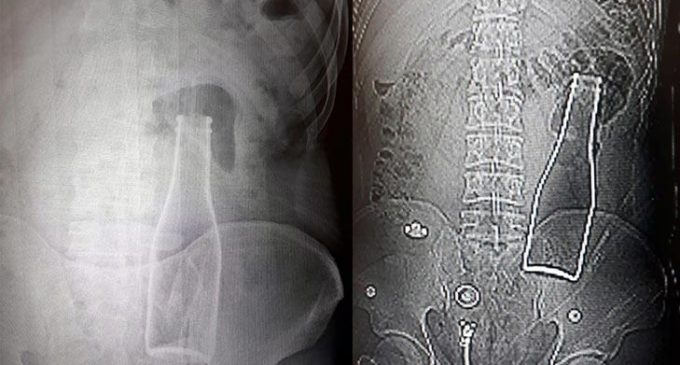

Karın ağrısı şikayetiyle gitti: Doktorlar şoke oldu!

Vücudundan şişe çıkan genç konuştu: Yanlışlıkla oldu